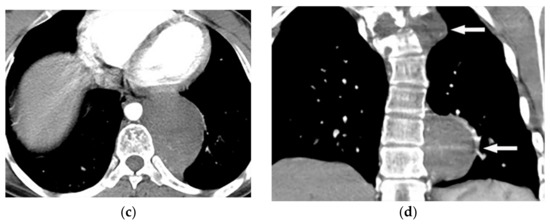

Malignant mesothelioma is the most common primary tumor of the pleura, which is related to prior asbestos exposure with a relatively poor prognosis [56].

Multidetector CT effectively reveals the primary tumoral extension, lymphadenopathy, and extrathoracic metastasis (Figure 27 and Figure 28) [56]. Another CT finding is circumferential pleural thickening (most common finding) with extension along the fissures. Large or punctate osseous or cartilaginous differentiation is more in favor of malignant mesothelioma rather than linear calcification that usually occurs within asbestosis plaques. Dynamic contrast-enhanced computed tomography (DCE CT) enables measuring intratumoral capillary permeability and blood flow, which are beneficial in evaluating treatment response [56,57,58].

Figure 27.

A 67-year-old man with dyspnea and chest pain. Contrast-enhanced CT in axial (a) and coronal (b) planes demonstrate left-sided localized enhancing pleural mass (arrow) with internal areas of necrosis that extend to the posteromedial aspect of the chest wall. Involvement of diaphragmatic pleura and elevation of left hemidiaphragm are also identified.

Figure 28.

A 70-year-old man with dyspnea. The non-contrast CT in the axial plane demonstrates right-sided large pleural effusion, near complete collapse of the right lung (a) after the chest tube insertion; thick circumferential nodular pleural thickening of parietal pleura was shown (arrow) (b). Contrast-enhanced CT of the upper abdomen shows the extension of mesothelioma through the abdominal cavity and wall with indentation over adjacent liver parenchyma (arrow) (c).

MR imaging and 18F-FDG PET/CT are useful in further evaluation of chest wall, diaphragm, and mediastinal invasion [56,57,58,59]. Malignant mesothelioma appears as unilateral hyperintense pleural effusion and pleural thickening with iso to slight hyperintensity to chest wall muscles on T1-weighted and moderate hyperintensity on T2-weighted images. Post-contrast enhancement is expected (Table 3). It is believed that higher metabolic activity on 18F-FDG PET/CT is associated with poor prognosis and shorter survival time [25,56,57,58].